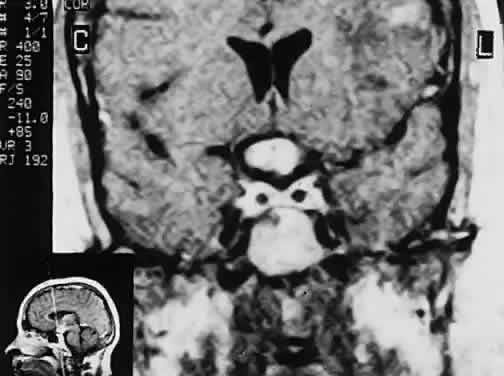

Fig. 2. Large prolactinoma. Original vision in the right eye (RE) was 8/200, left eye (LE) 1/200, with serum prolactin of 26,000 ng/ml and galactorrhea. Four months of bromocriptine reduced prolactin to 661 ng/ml, vision improved to RE 20/40, LE 20/50. At 3 years, vision was as follows: RE 20/30, LE 20/20; prolactin was 25.9 ng/ml. Enhanced magnetic resonance imaging. Sagittal (A) and coronal (C) images at diagnosis. Sagittal (B) and coronal (D) images at 2-year follow-up, showing dramatic shrinkage of the mass.

In addition to the radiologic implications mentioned previously, specific points should be emphasized. Contrast-enhanced CT and, especially, MRI have replaced all previous radiologic techniques in the detection and anatomic assessment of sellar and juxtasellar lesions. MRI has also the inherent advantage of using no radiation, nor does it require iodinated contrast injections. Although thin-section contrasted CT does indeed disclose most lesions, bone changes, and recent hemorrhage, MRI is superior in delineating distortions of optic nerves and chiasm, in displaying arteries, and in revealing fat, hemorrhage, or cyst (see Figs. 3E through M). Indeed, in a prospective study of normal volunteers, gadolinium-enhanced MRI disclosed pituitary adenomas (3 mm to 6 mm in diameter, i.e., microadenomas) in 10% of adults aged 18 to 60 years.66 T2-weighted fast spin-echo MRIs are currently the most precise sequence for demonstrating the optic nerves and chiasm, even when these structures are severely distorted by suprasellar tumor extension.67